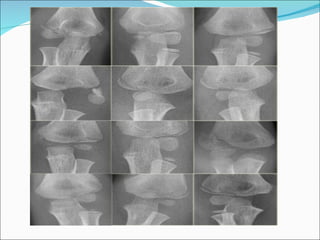

RADIOGRAPHYnot ossified then

โ€ขRadiographs if the lateral condyle and capitellum have

โ€ขradiographic findings can be subtle

โ€ขcontra-lateral radiographs are very important

โ€ขinternal oblique view most accurately shows maximum displacement and

fracture pattern,

- with the arm internally rotated will best demonstrate amount of

displacement & rotation of lateral condyle fragment;

- often multiple oblique radiographs will be needed to accurately

determine whether frx is displaced or non displaced;

Lateral Condyle fractures x rays .

The diagnosis of a lateral condyle fracture can be challenging.

Fracture lines are sometimes barely visible .

Remembering the fact that the lateral condyle fracture is the second most common

elbow-fracture in children and because you know where to look for will help you

lateral condyle fracture. On the x-ray only a small metaphyseal fragment is

visible. The detatched fragment however is larger than it appears on the

radiograph. The fracture extents into the lateral ridge of the trochlea. Elbow is

probably unstable.